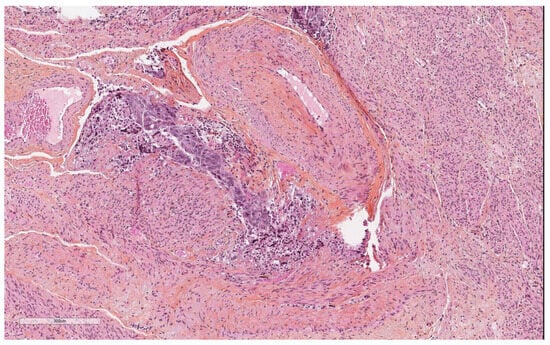

Artefacts in Hysterectomies with a Special Focus on Vascular Pseudoinvasion

| Vascular pseudoinvasion | |

| Present | 14 (23.7) |

| Absent | 46 (76.6) |

| Myometrial clefts | |||

| Present | 10 | 6 | <0.001 |

| Absent | 4 | 40 | |